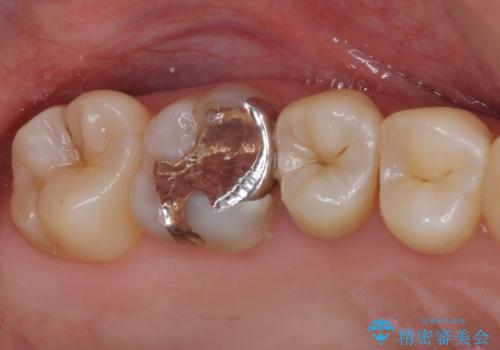

- 冷たいものがしみるとのことで来院された患者様です。

レントゲン写真より、第一小臼歯にやや大きい虫歯があることが分かりました。

症状などから診断したところ、神経を取る可能性は低いと考えられたため、セラミックインレーによる修復治療を行うこととしました。

奥の大臼歯にもむし歯があったので、一緒に処置を行いました。